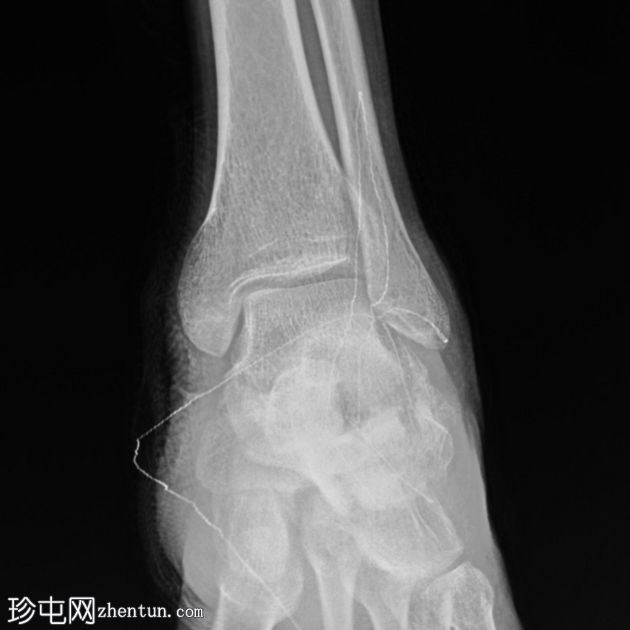

正位片

关节内粉碎性跟骨骨折(侧位/轴位片)。

未见其他骨折或下胫腓联合损伤。

绷带中的放射性标记物造成伪影。

可以评估Böhler角和Gissane角,尤其是在初始影像检查中关节内骨折延伸不明显的情况下。本例中,Böhler角减小,Gissane角增大。这两个发现均证实了关节内跟骨骨折。